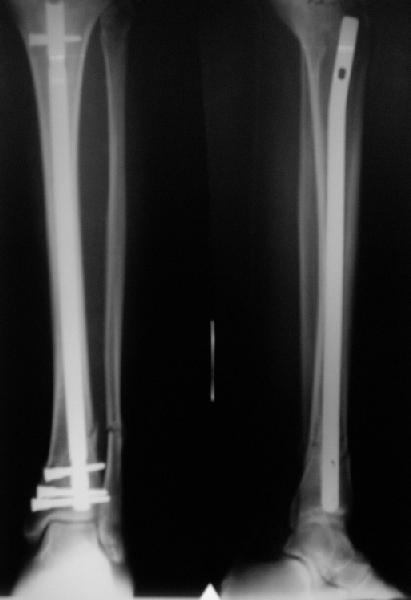

A typical case is attached, also an image with intra-op reduction obtained by a small wire distractor, in the moment of insertion a Poller wire in AP direction. Fixation by a SIGN nail. Despite the fibula was not fixed healing was obtained with the unchanged alignment.